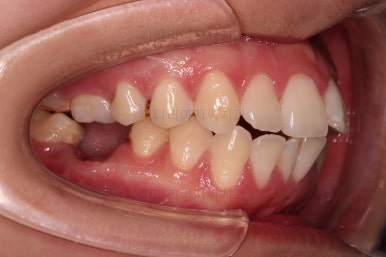

마찬가지로 초진 시 입안의 모습입니다.

입안 사진을 보니 문제점이 보이죠.

바로 어금니가 없는 상태였습니다.

물론 치열도 그리 많이 삐뚠 편은 아니고, 치아가 없으니 심플하게 임플란트를 해 넣으면 되지 않겠나 라고 생각할 수 있지만요.

나이도 많이 어리시고, 임플란트를 한다는 심리적 저항감도 있었고요.

한 번 임플란트를 해 넣으면 교정치료가 매우 힘들어진다는 점과 겸사겸사 돌출감도 개선하고자 하는 의지가 있으셔서 임플란트 없이 사랑니를 살려서 어금니 대신 쓰는 부산사랑니교정 치료를 해보기로 했습니다.